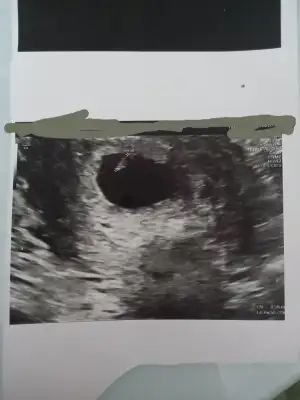

Merhaba tahminde bulunurmusunMaalesef üreme organını göremedim

CİNSİYET TAHMİNİİİİİ

Kimler kimler yazdı?Ueni fotoğrafı var bu gün gittik hiç hareket etmedi böbrek için ultrasona gittik o doktor erkek5. Bebek benim görüşüm dediNubunu kapatmis kafa yapisi yuvarlak kiz olbilir genelde koseli olunca erkek oluyo

Bence erkek bariz belli.Eki Görüntüle 3178479 bize de erkek dedi 16, haftadayız sizce yanılma payı olabilir mi ikinci fotoğraftaki organı mı acaba

Benim 7 haftalık bakabilirmisiniz acaba rica etsenÇok tutarlı diyemem ama ben hamileyken arkadaşlarla hep dikkat etmiştik kız bebeğin başı sağda erkek bebeğin başı solda oluyodu ultrason fotosunda varsayım yani7-8 haftalık fotosu varsa daha net söyleyebilirim ama

Cnm fotoyu goremedimBenim 7 haftalık bakabilirmisiniz acaba rica etsen

Attim cnmCnm fotoyu goremedim

7 haftalık

Gülüm erkek diyebilirim hayirli olsun7 haftalık

Çok tutarlı diyemem ama ben hamileyken arkadaşlarla hep dikkat etmiştik kız bebeğin başı sağda erkek bebeğin başı solda oluyodu ultrason fotosunda varsayım yani7-8 haftalık fotosu varsa daha net söyleyebilirim ama